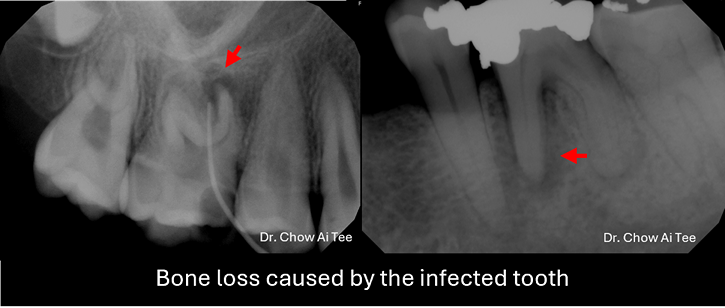

Fortunately, pulling out a tooth is no longer the go-to solution. In most cases, root canal treatment (endodontic therapy) offers a way to preserve the natural tooth. During this procedure, the dentist removes damaged and infected pulp tissue from the tooth, ensuring proper oral function. The first step involves assessing the tooth, identifying the problem, and planning the treatment. Dental X-rays and other diagnostic tools help determine the extent of damage.